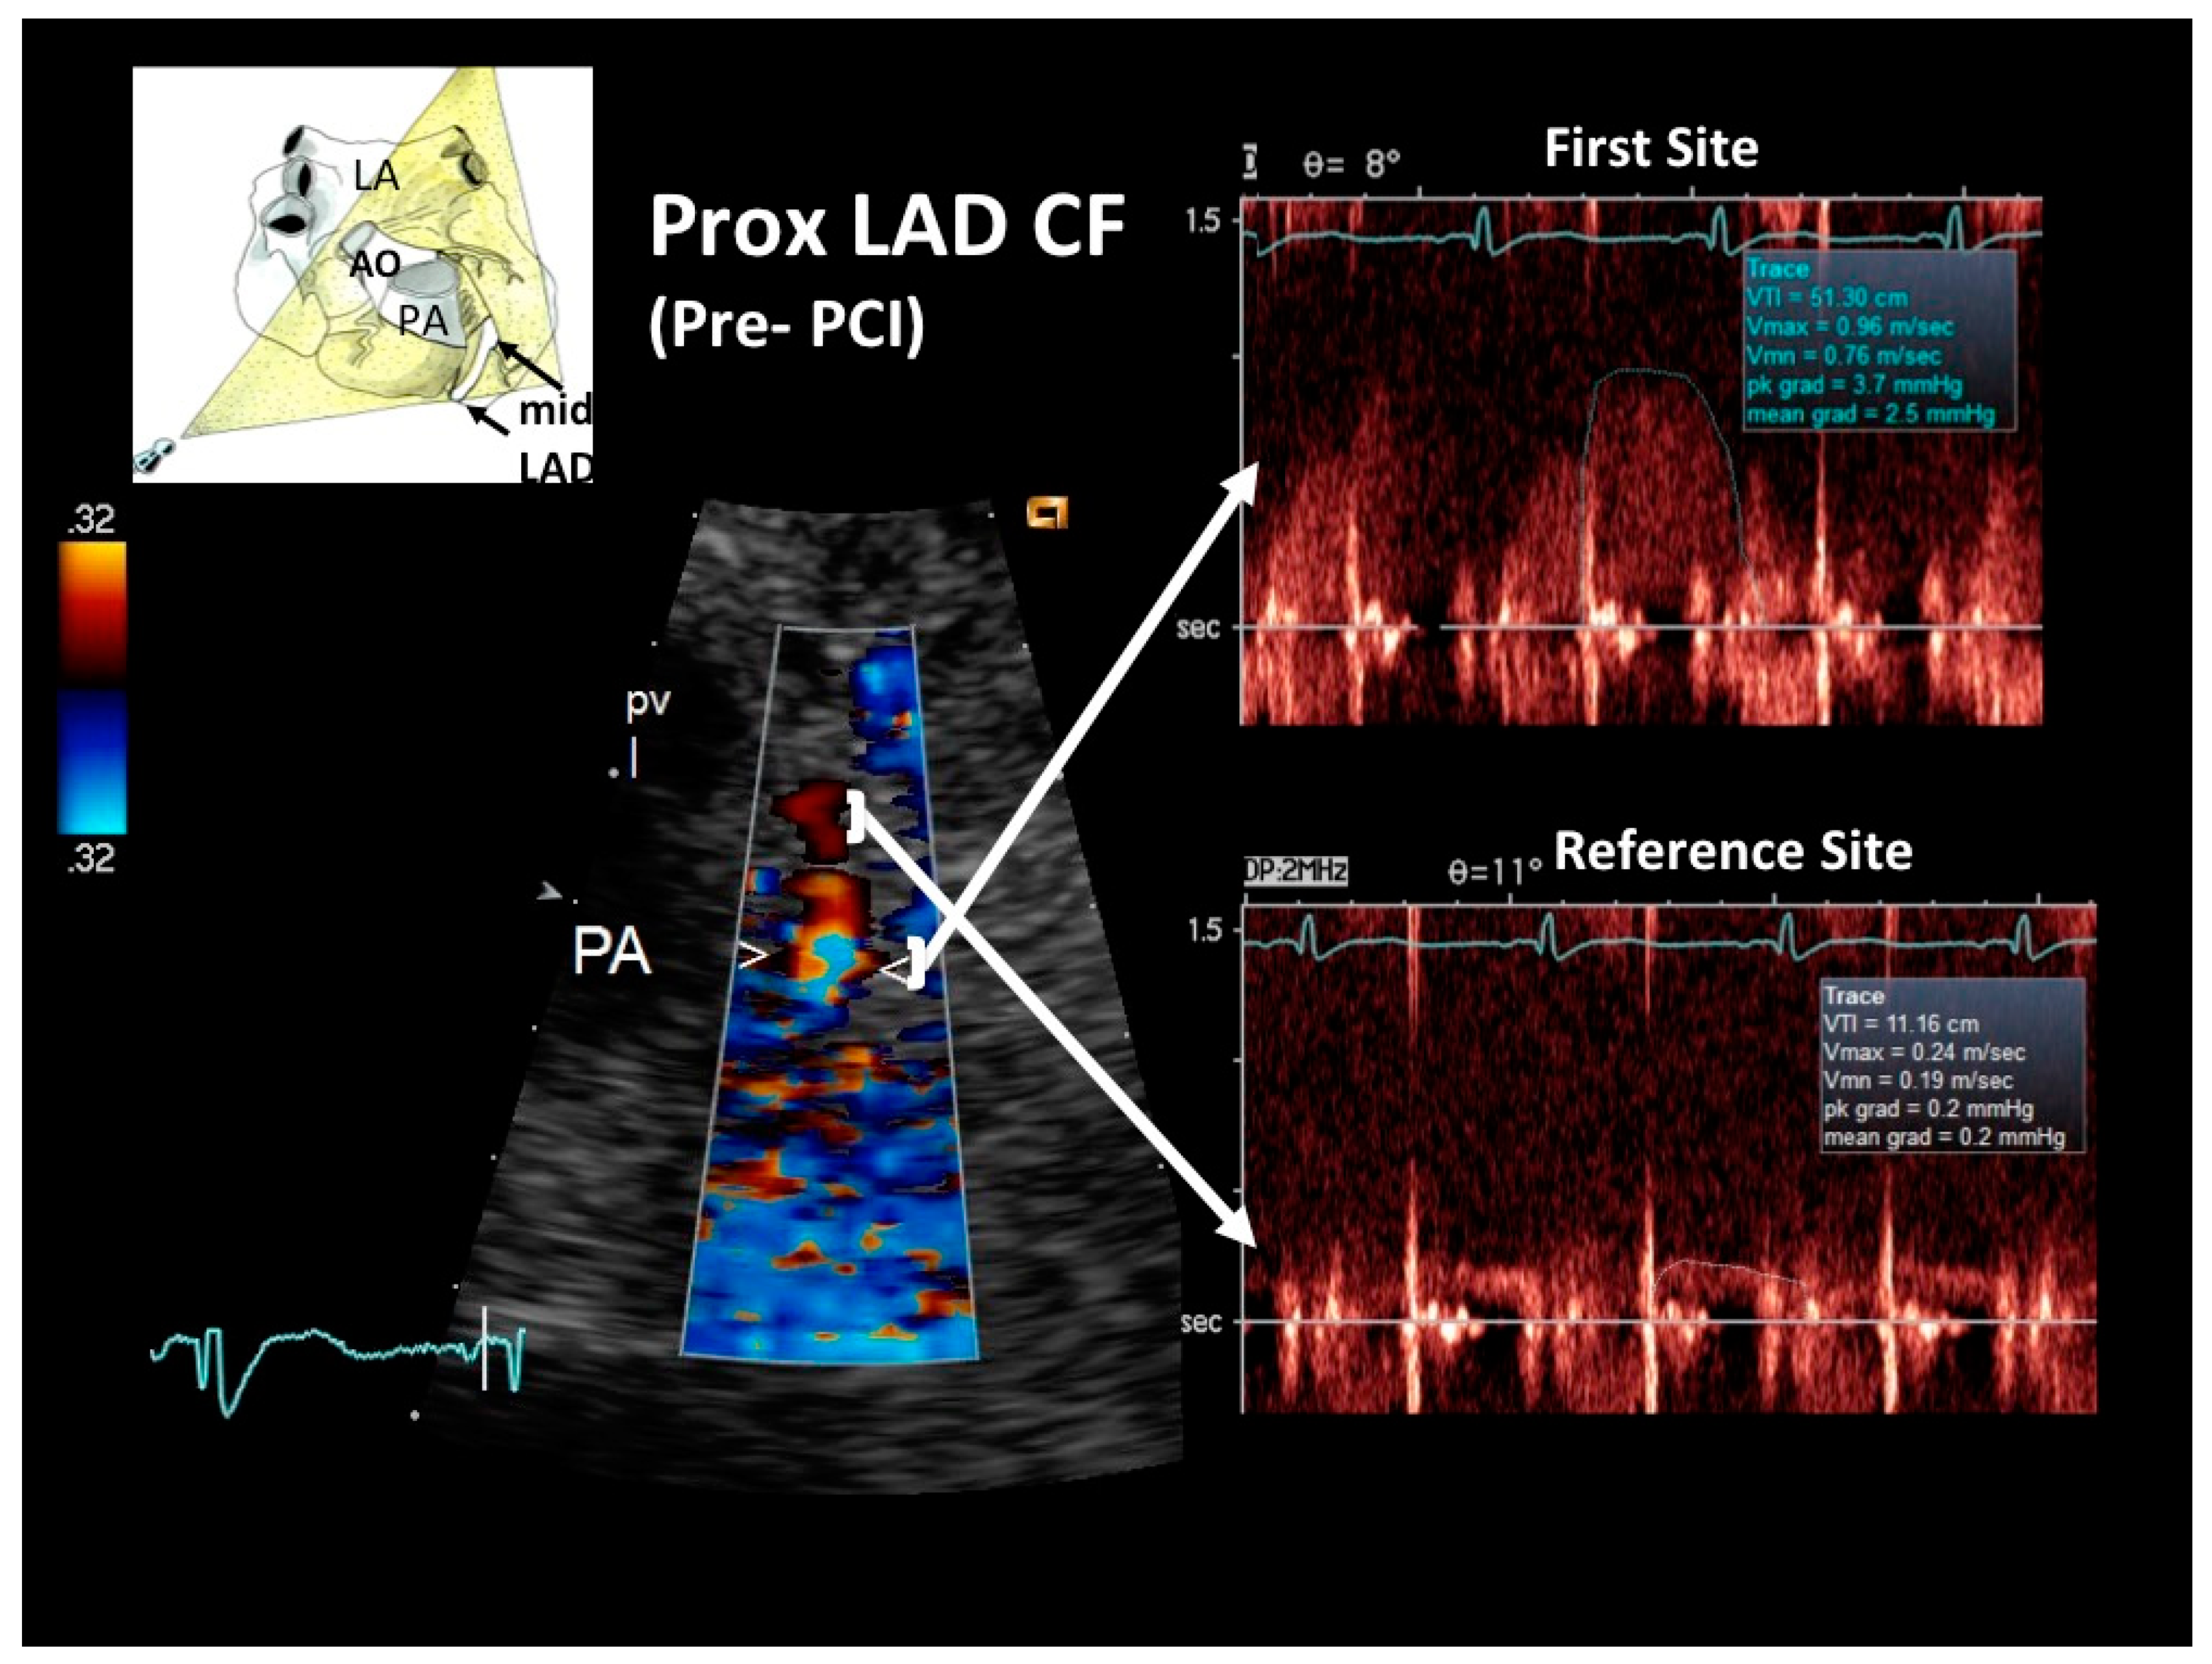

Figure 2. Blood flow Doppler recording by E-Doppler TTE in the proximal LAD, offering a modified short-axis view of the base of the heart in the acute phase. On the left, color flow in the proximal LAD shows a limited area of considerably accelerated BFV expressed by aliased signals (arrowheads); some flushing artifacts are also present since the heart rate was suboptimally reduced, but they do not disturb the proper signal interpretation. PW Doppler sampling (on the right) at the color-aliased signal confirms a critical increase of blood flow velocity compared to the distal reference area (upper and lower arrows connect the sampling color area to the corresponding PW Doppler tracing). Application of the continuity equation yields an 89% stenosis area. A cartoon indicating the plane orientation is shown on the upper left. The diastolic waves of the Doppler tracings are outlined in blue. LAD = left anterior descending coronary artery; PW = pulsed wave; CF = coronary flow; RVOT = right ventricular outflow tract; PV = pulmonary valve; PA = pulmonary artery; LA = left atrium.

General echocardiography revealed marked apical and anterior septal wall hypokinesia, with a globally preserved left ventricular systolic function but marked telediastolic restriction, as assessed by pulmonary venous flow Doppler recording. The latter showed a high peak and markedly prolonged duration of reversal of pulmonary venous flow [17]. E-Doppler TTE allowed a flow velocity Doppler recording to be made in the LMCA and in the entire LAD. Findings were markedly abnormal, recording a locally accelerated and turbulent flow at the end of the proximal LAD tract, as revealed by color-guided PW Doppler recording indicating significant stenosis (Figure 2). By applying the continuity equation, which has been amply validated with this approach [12,13,18], the stenosis was quantified as severe (89% of area reduction). Coronary flow reserve (CFR) was not measured due to the critical setting.

As expected, the reference distal flow velocity was low (Figure 2) and mildly increased after PCI (Figure 5). A long severe stenosis can reduce basal flow and flow velocity distally to the obstruction. This, however, does not hamper stenosis severity assessment by the continuity equation as previously demonstrated. Even if the stenosis is very severe (>85% diameter narrowing) and there is a reduction at rest of the flow distally to the stenosis, as demonstrated by the landmark Gould study [36], the flow at the stenosis and in the post-pre-stenotic segments must be the same. This arises on the basis of the principle of continuity of flow, which is a corollary of the law of conservation of mass, which states that the flow in any portion of a non-branching tube is equal: what comes in must come out [25]. Problems can arise in cases of collaterals between the stenosis and the sampling site, since flow could be diverged to the collaterals and so create flow differences between the sampling site and the stenosis, causing inaccurate estimation of the % lumen narrowing with the continuity equation [37,38]. However, as demonstrated in a recent in vitro study [38], since there is a certain pressure drop in the post-stenotic segment, such a divergent flow to collaterals is much less important in cases of sampling distally to the stenosis than proximally, owing to a reduced driving pressure toward collaterals in the distal compared to the proximal segments. Therefore, the authors of that paper suggest that as a general rule, it is better to sample the reference distally (as in our case) rather than proximally, owing to the risk of such collaterals.